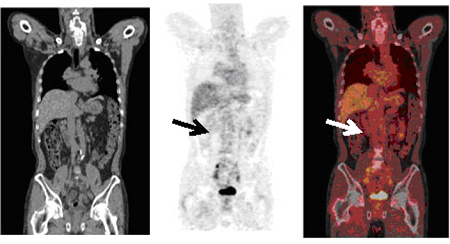

PET/CTの写真

大腸がん/再発

大腸がん/リンパ節転移